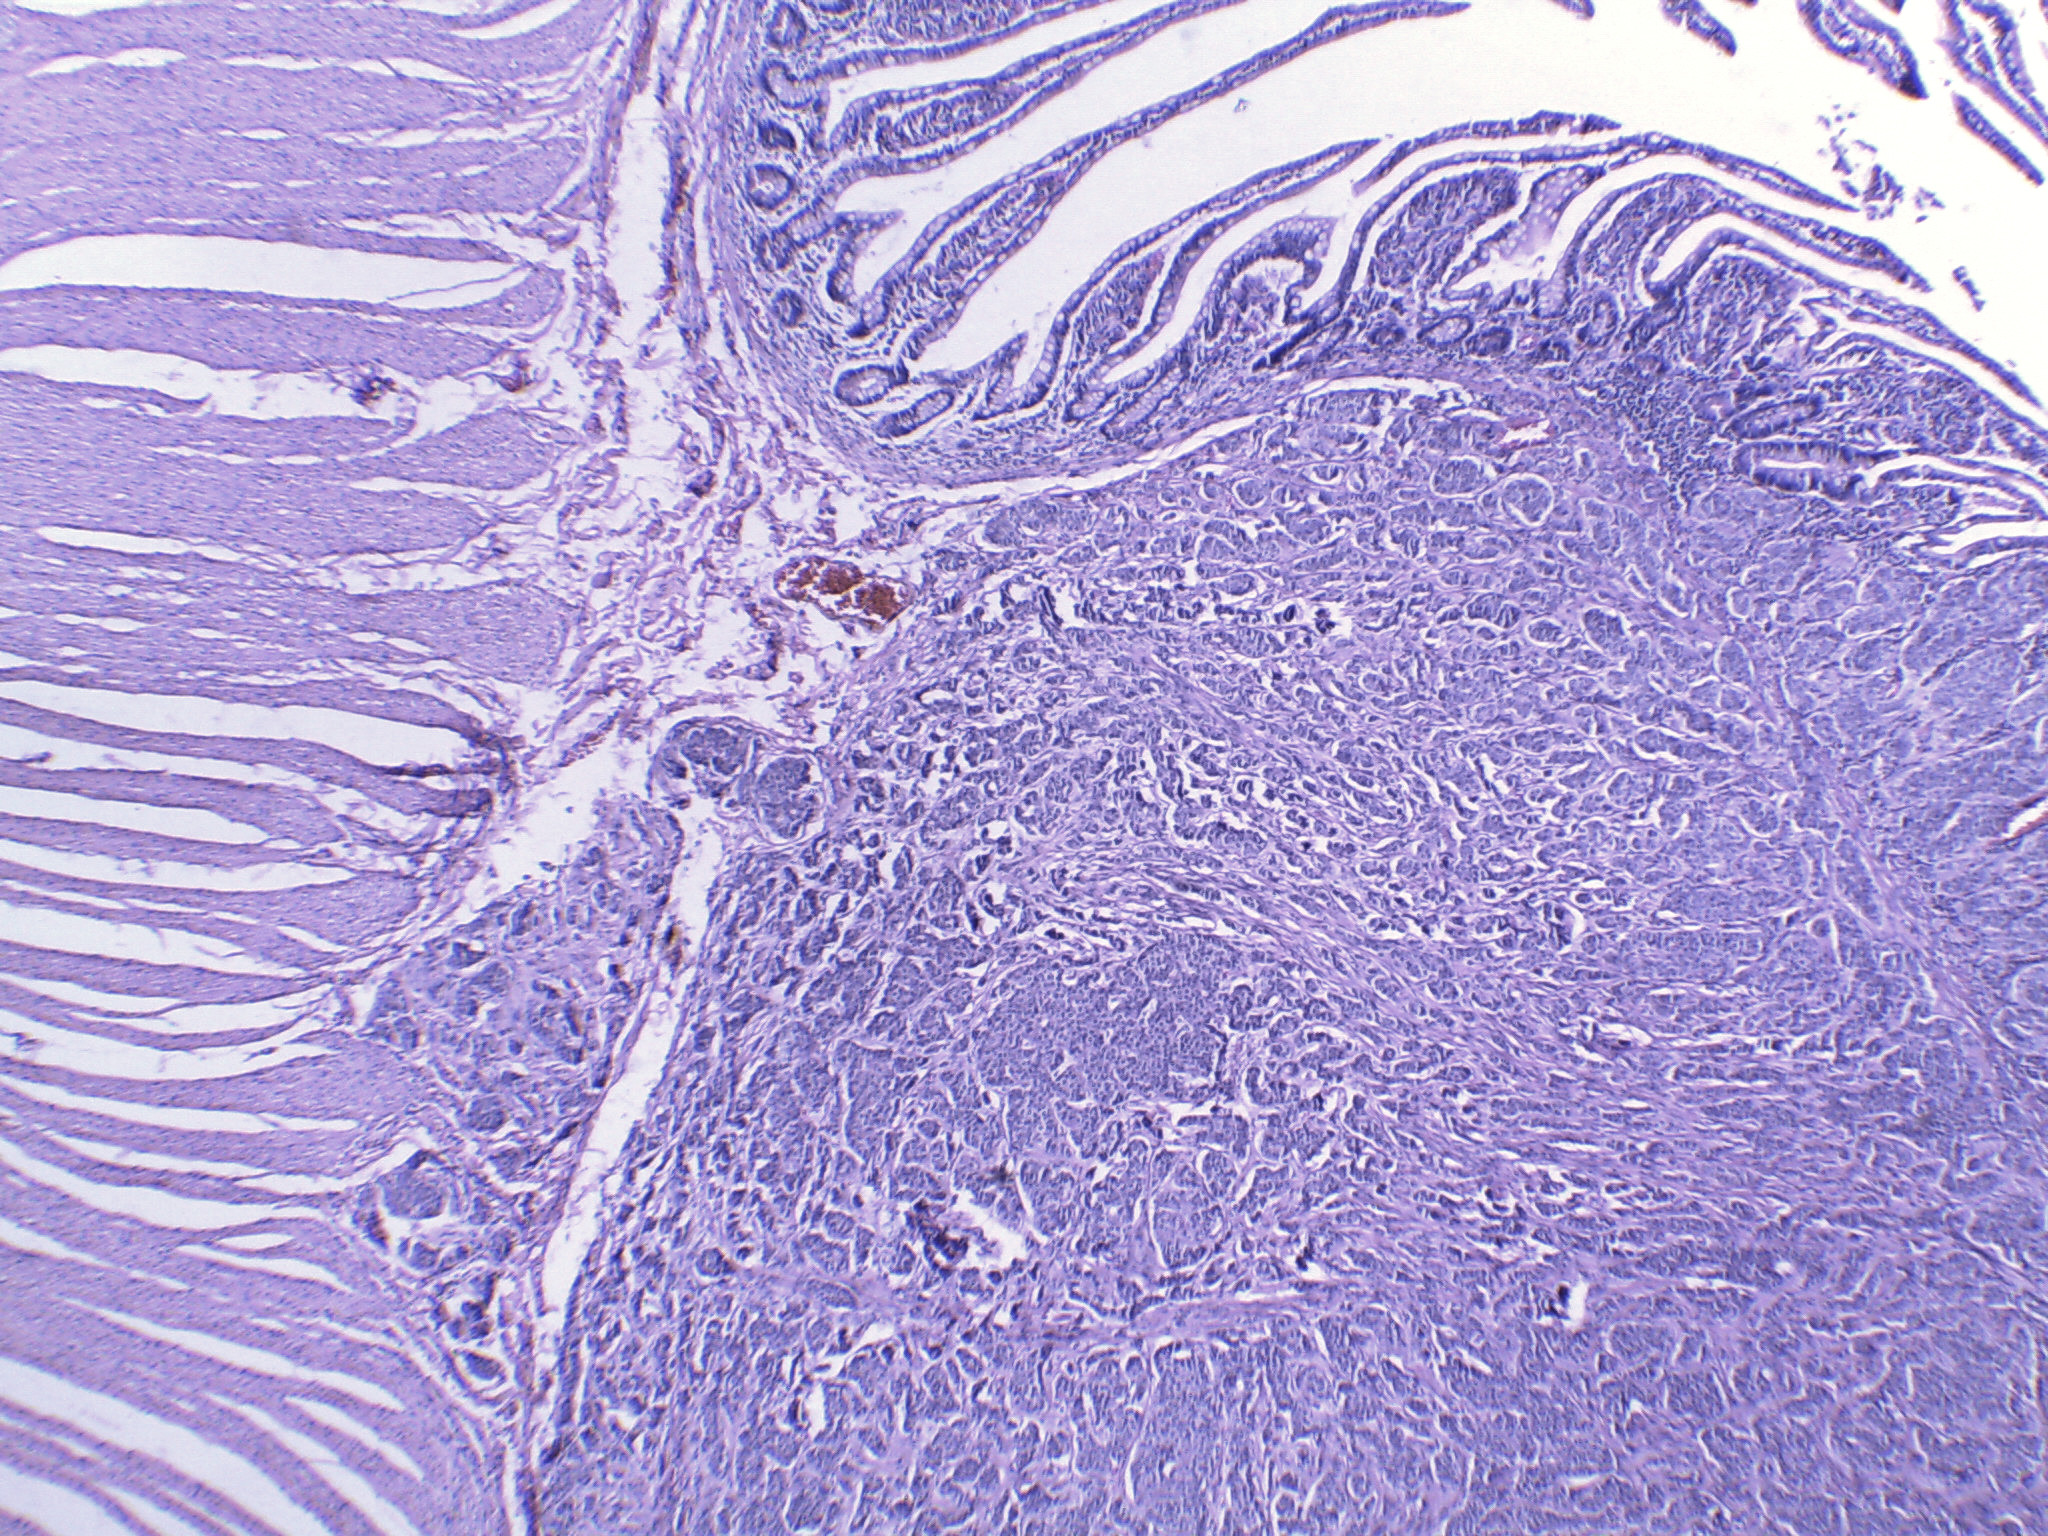

Hombre de 55 años con padecimiento de 1 año de evolución caracterizado por melena, astenia, adinamia y anemia. En enteroscopía se observaron múltiples lesiones subepiteliales en intestino delgado de una de las cuales se tomó biopsia.

Se realizó cirugía en la que se identificaron múltiples nódulos en ileon , entre los 80 y 120 cm de la válvula ileocecal. Se procedió a resección segmentaria de intestino.

Biopsia:

Tumor neuroendocrino bien diferenciado grado 1